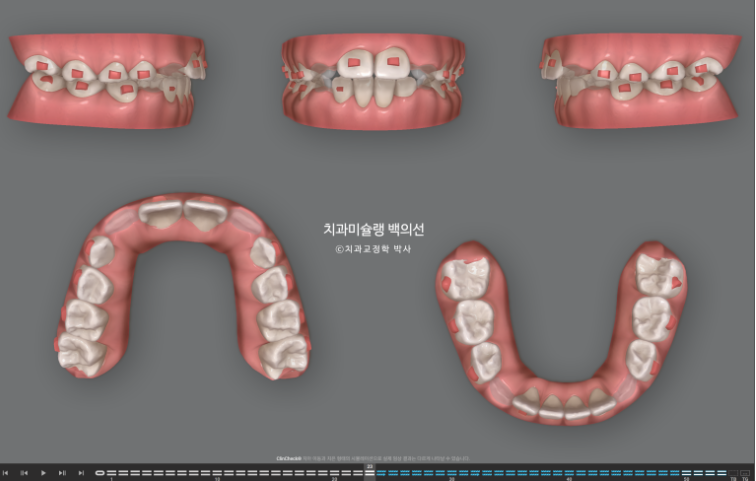

파란화살표 부분을 보자면

장치 양옆에 날개처럼 튀어나온 부분이 Wing 이며 이 부분이 아래턱의 위치를 정상위로 유도합니다.

23.11

사진의 파란화살표처럼 위 아래 윙 끼리 엇갈려 물리며 아래턱을 전방위치 시키며, 최대성장기와 맞물리면 하악골 성장까지 유도하게 됩니다.

23년 11월 24년 7월까지 53번 마지막 장치까지 다 끼면서 MA 단계를 마쳤습니다.